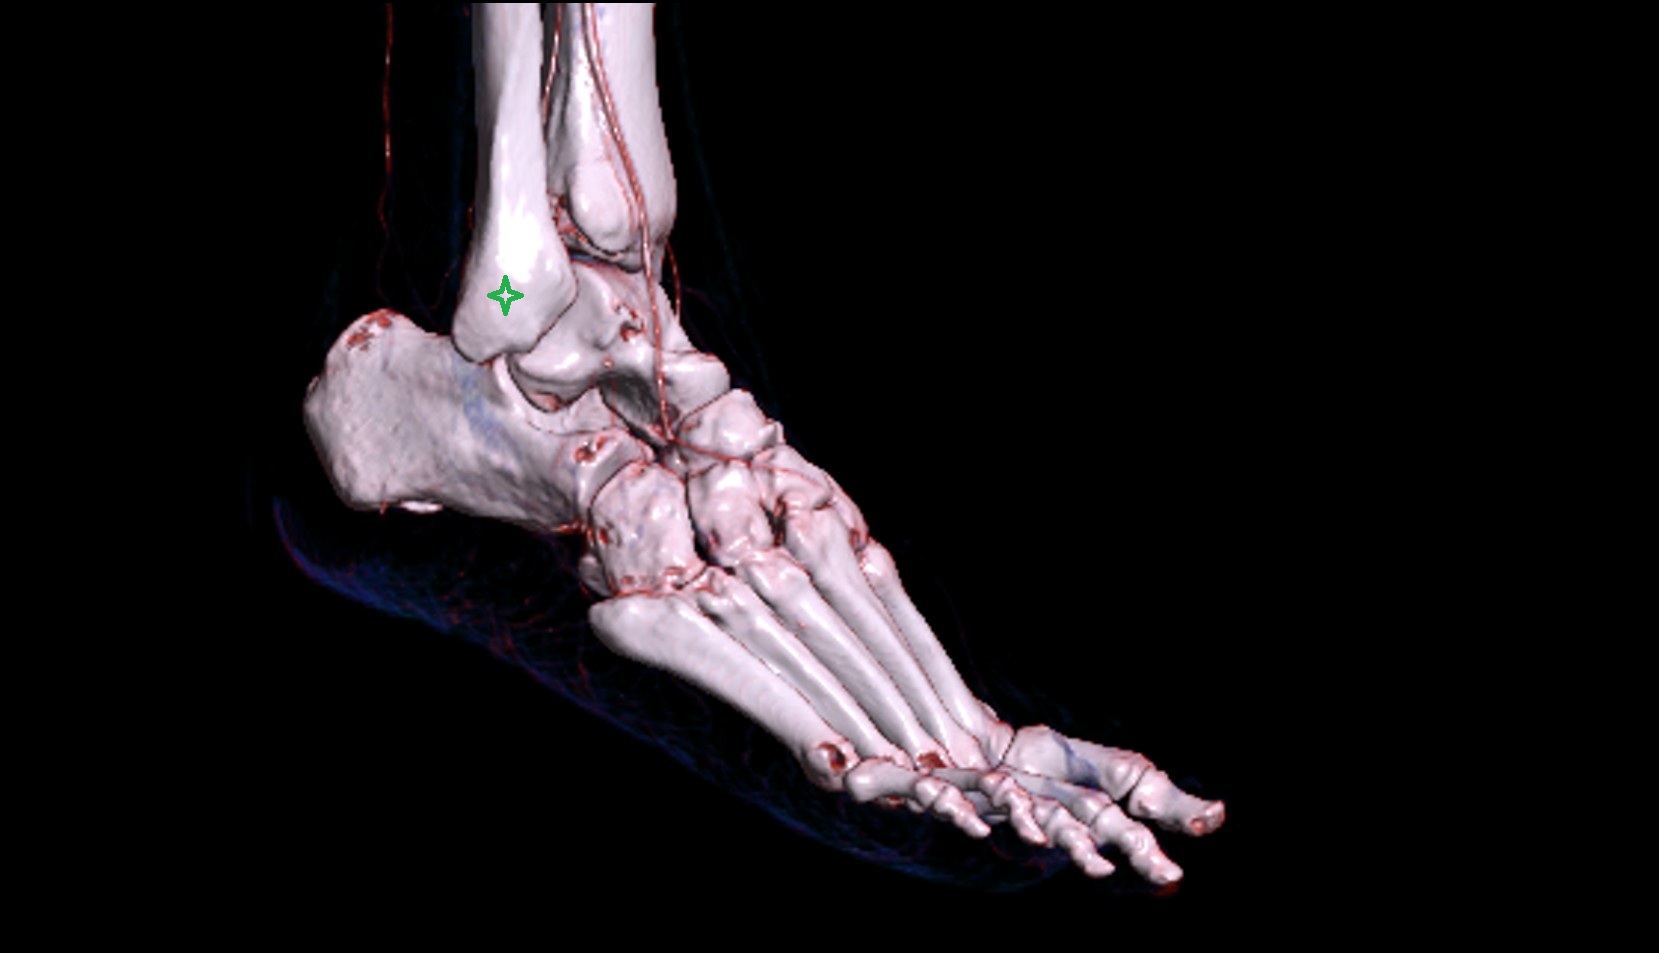

- Talus

- Head of talus

- Body of talus

- Neck of talus

- Calcaneus

- Anterior process of calcaneus

- Sustentaculum tali

- Cuboid

- Medial malleolus

- Lateral malleolus

- Ankle joint

- Talocalcaneal joint

- Talocalcaneonavicular joint

- Calcaneocuboid joint